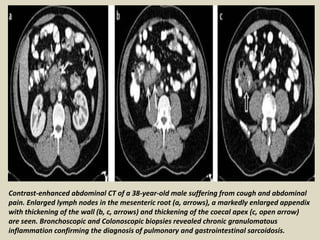

Contrast-enhanced abdominal CT of a 38-year-old male suffering from cough and abdominal

pain. Enlarged lymph nodes in the mesenteric root (a, arrows), a markedly enlarged appendix

with thickening of the wall (b, c, arrows) and thickening of the coecal apex (c, open arrow)

are seen. Bronchoscopic and Colonoscopic biopsies revealed chronic granulomatous

inflammation confirming the diagnosis of pulmonary and gastrointestinal sarcoidosis.